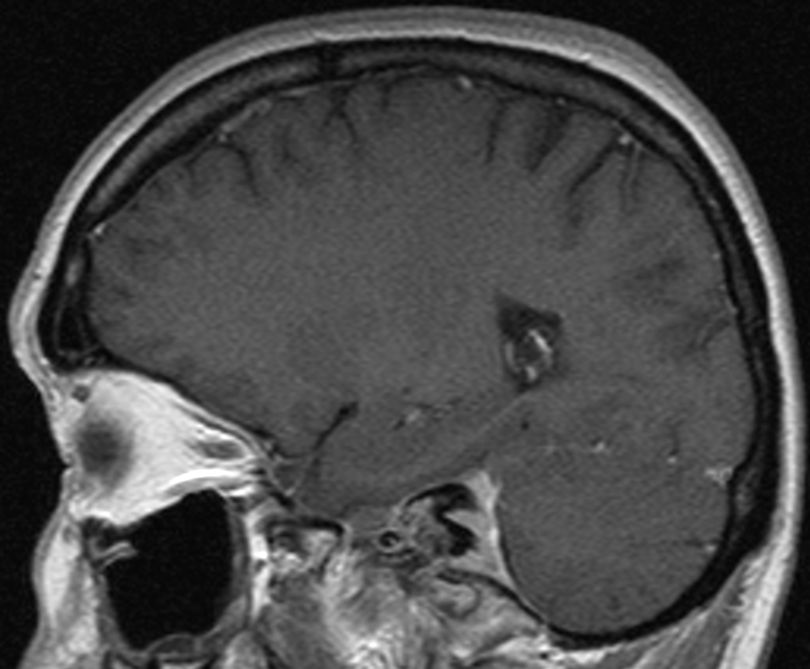

| MRT eines Meningeoms des Tentoriums |

| 72-jährige Patientin mit Teilparese des rechten Beins, passageren Sprachstörungen und Krampfanfall vor 6 Monaten. Postoperative Histologie: Meningeom Grad 1 | CT vor KM-Gabe . |